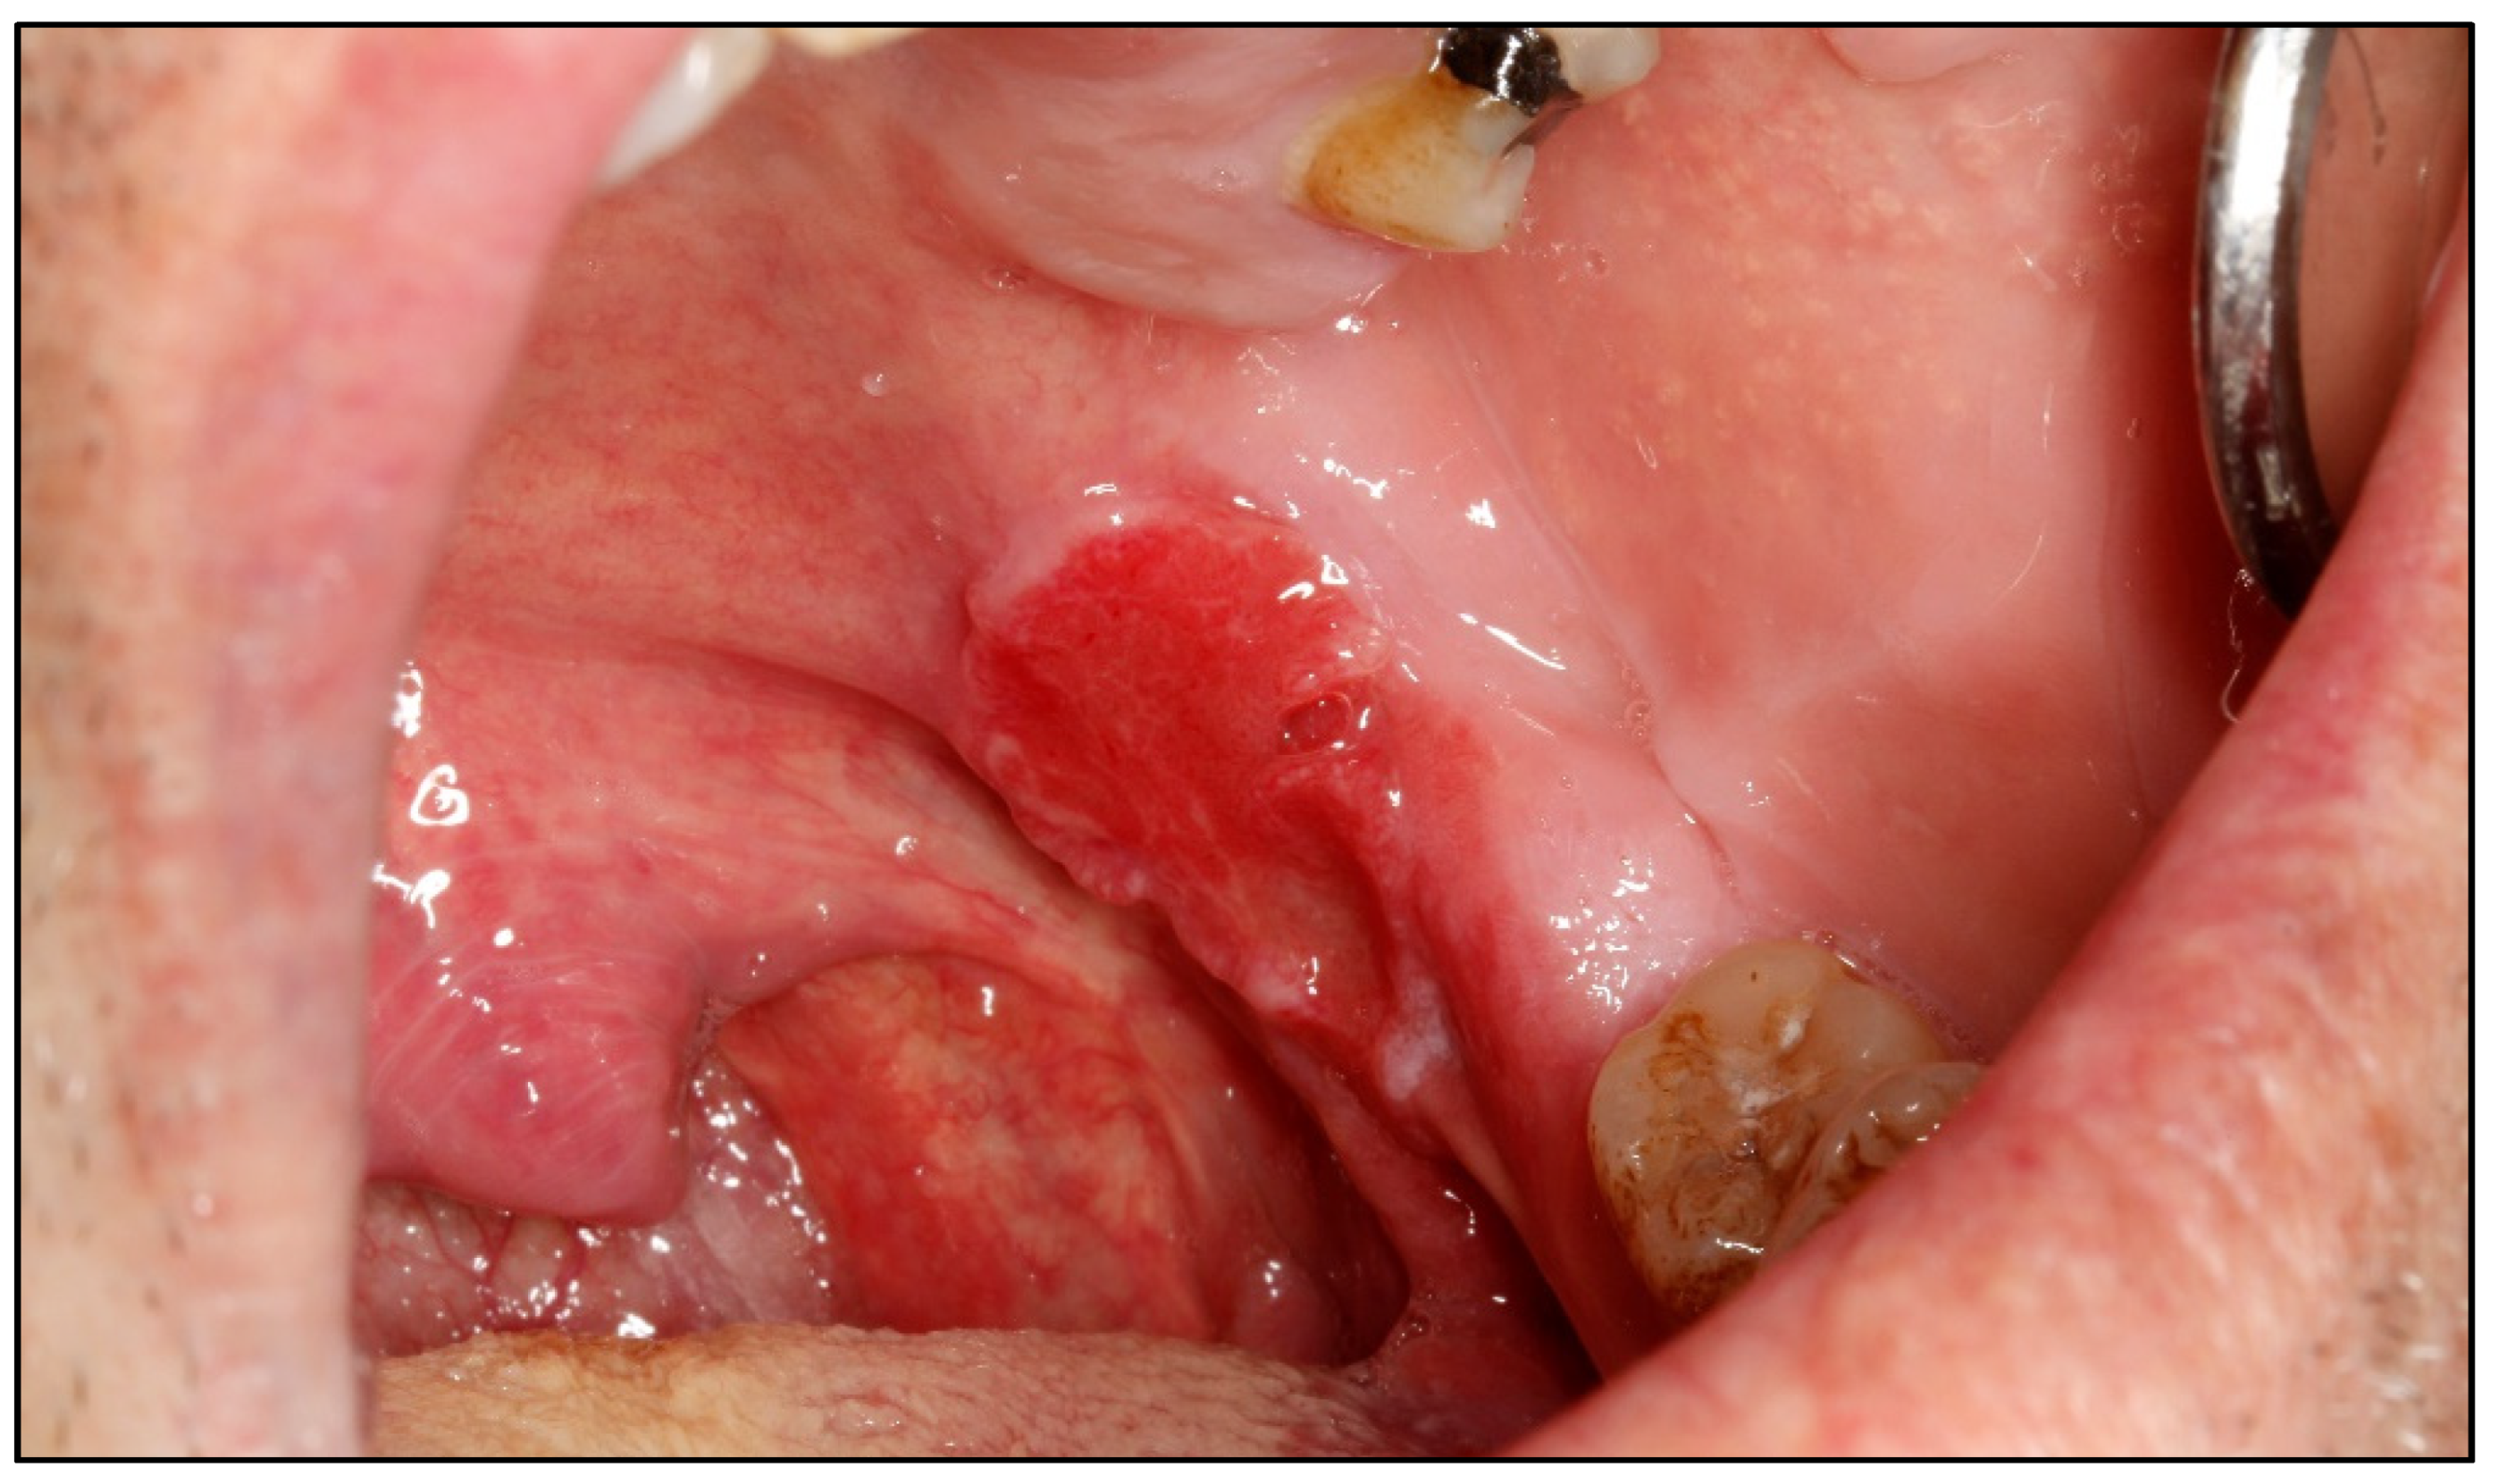

Appendix A. Clinical Presentation of OPMD